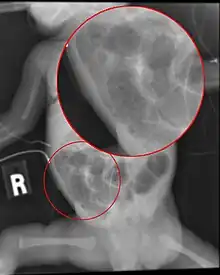

Diagnosis is usually suspected clinically, but often requires the aid of diagnostic imaging, most commonly radiography, which can show the intestines and may show areas with death tissue or a bowel perforation.[18] Specific radiographic signs of NEC are associated with specific Bell's stages of the disease:[19]

- Specific radiologic signs (pneumatosis intestinalis or portal venous gas)

- Severe radiologic signs (pneumoperitoneum)

Ultrasonography has proven to be useful, as it may detect signs and complications of NEC before they are evident on radiographs, specifically in cases that involve a paucity of bowel gas, a gasless abdomen, or a sentinel loop.[21] Diagnosis is ultimately made in 5–10% of very-low-birth-weight infants (<1,500g).[22]

Alimentary tract of infant showing intestinal necrosis, pneumatosis intestinalis, and perforation site (arrow) (autopsy)

Close-up of intestine of infant showing necrosis and pneumatosis intestinalis (autopsy)

Diagnosis of NEC is more challenging in premature infants, due to inexplicit symptoms and radiographic signs. The most preterm infant is at highest risk of developing NEC.[23]